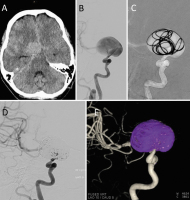

Neurovaskuläre Therapieoptionen bei komplexen Aneurysmen der Arteria carotis interna // Neurovascular therapeutic options in complex intracranial aneurysms

Journal für Neurologie, Neurochirurgie und Psychiatrie 2021; 22 (3): 128-134 Volltext (PDF) Summary Praxisrelevanz Abbildungen